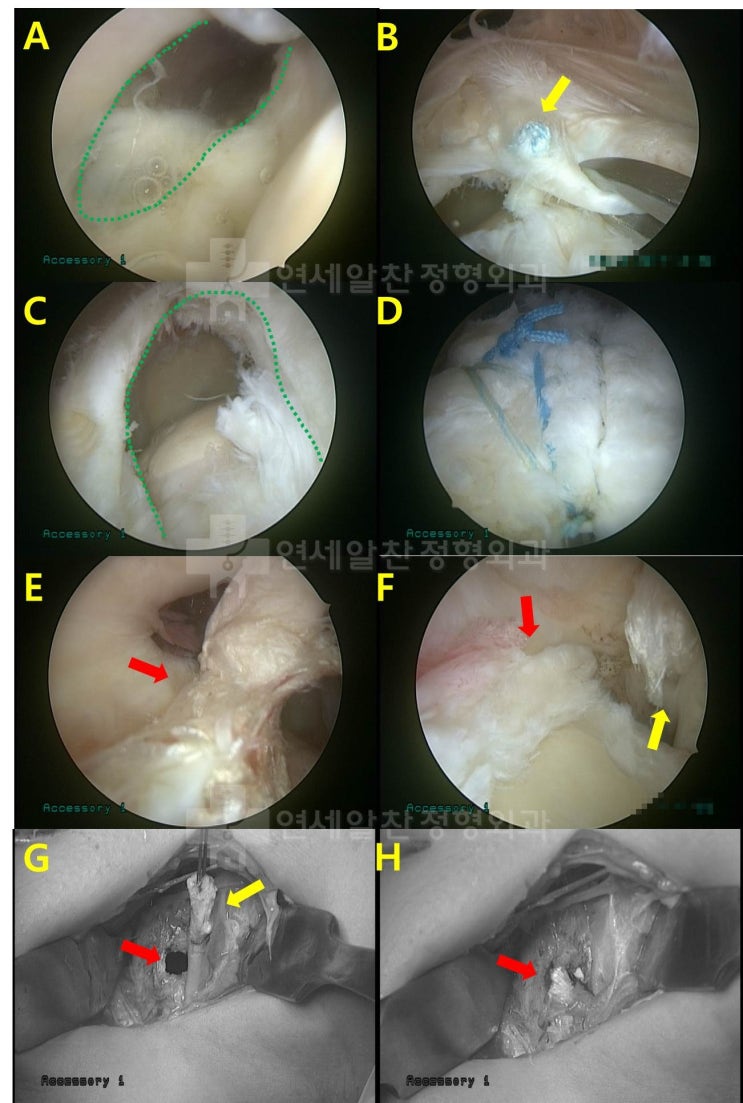

어깨 회전근개 파열 : 보다 단단하게 봉합하는 이열봉합법

안녕하세요. 정형외과 전문의 이동규 입니다. 오늘은 회전근개 파열에서 관절경 수술시 더 단단하게 봉합하...

회전근개파열 에서 이열교량형 봉합법 에 대한 고찰

회전근개 파열 을 수술할 경우 봉합법에 대한 문의를 하는 경우가 종종 있다. 회전근개파열 이 있는 경우 ...